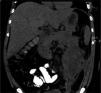

Quince días después, persiste evolución tórpida. La tomografía de control describió una colección encapsulada a nivel de la cola del páncreas y de la corredera parietocólica izquierda (fig. 1). Se decide realizar VARD. Cuarenta y cinco minutos previo a la cirugía se administraron 2.5ml de verde de indocianina diluidos en 5cc de solución salina. Se utilizó el catéter pigtail colocado en la línea axilar media izquierda 5cm superior de la espina ilíaca anterosuperior para introducir trocar de 12mm. Se realiza insuflación con CO2 hasta 12mmHg y, bajo visualización directa, se coloca un trocar de 5mm. Se aspira líquido de necrosis, obteniéndose 600cc de líquido purulento. Con ayuda de verde de indocianina se realizó desbridamiento del tejido desvitalizado, evitando el daño a estructuras vasculares y al conducto pancreático principal. Se realizó el lavado de cavidad con suero fisiológico y se retiró el catéter pigtail, colocándose un drenaje cerrado tipo Blake de 25FR (fig. 2).